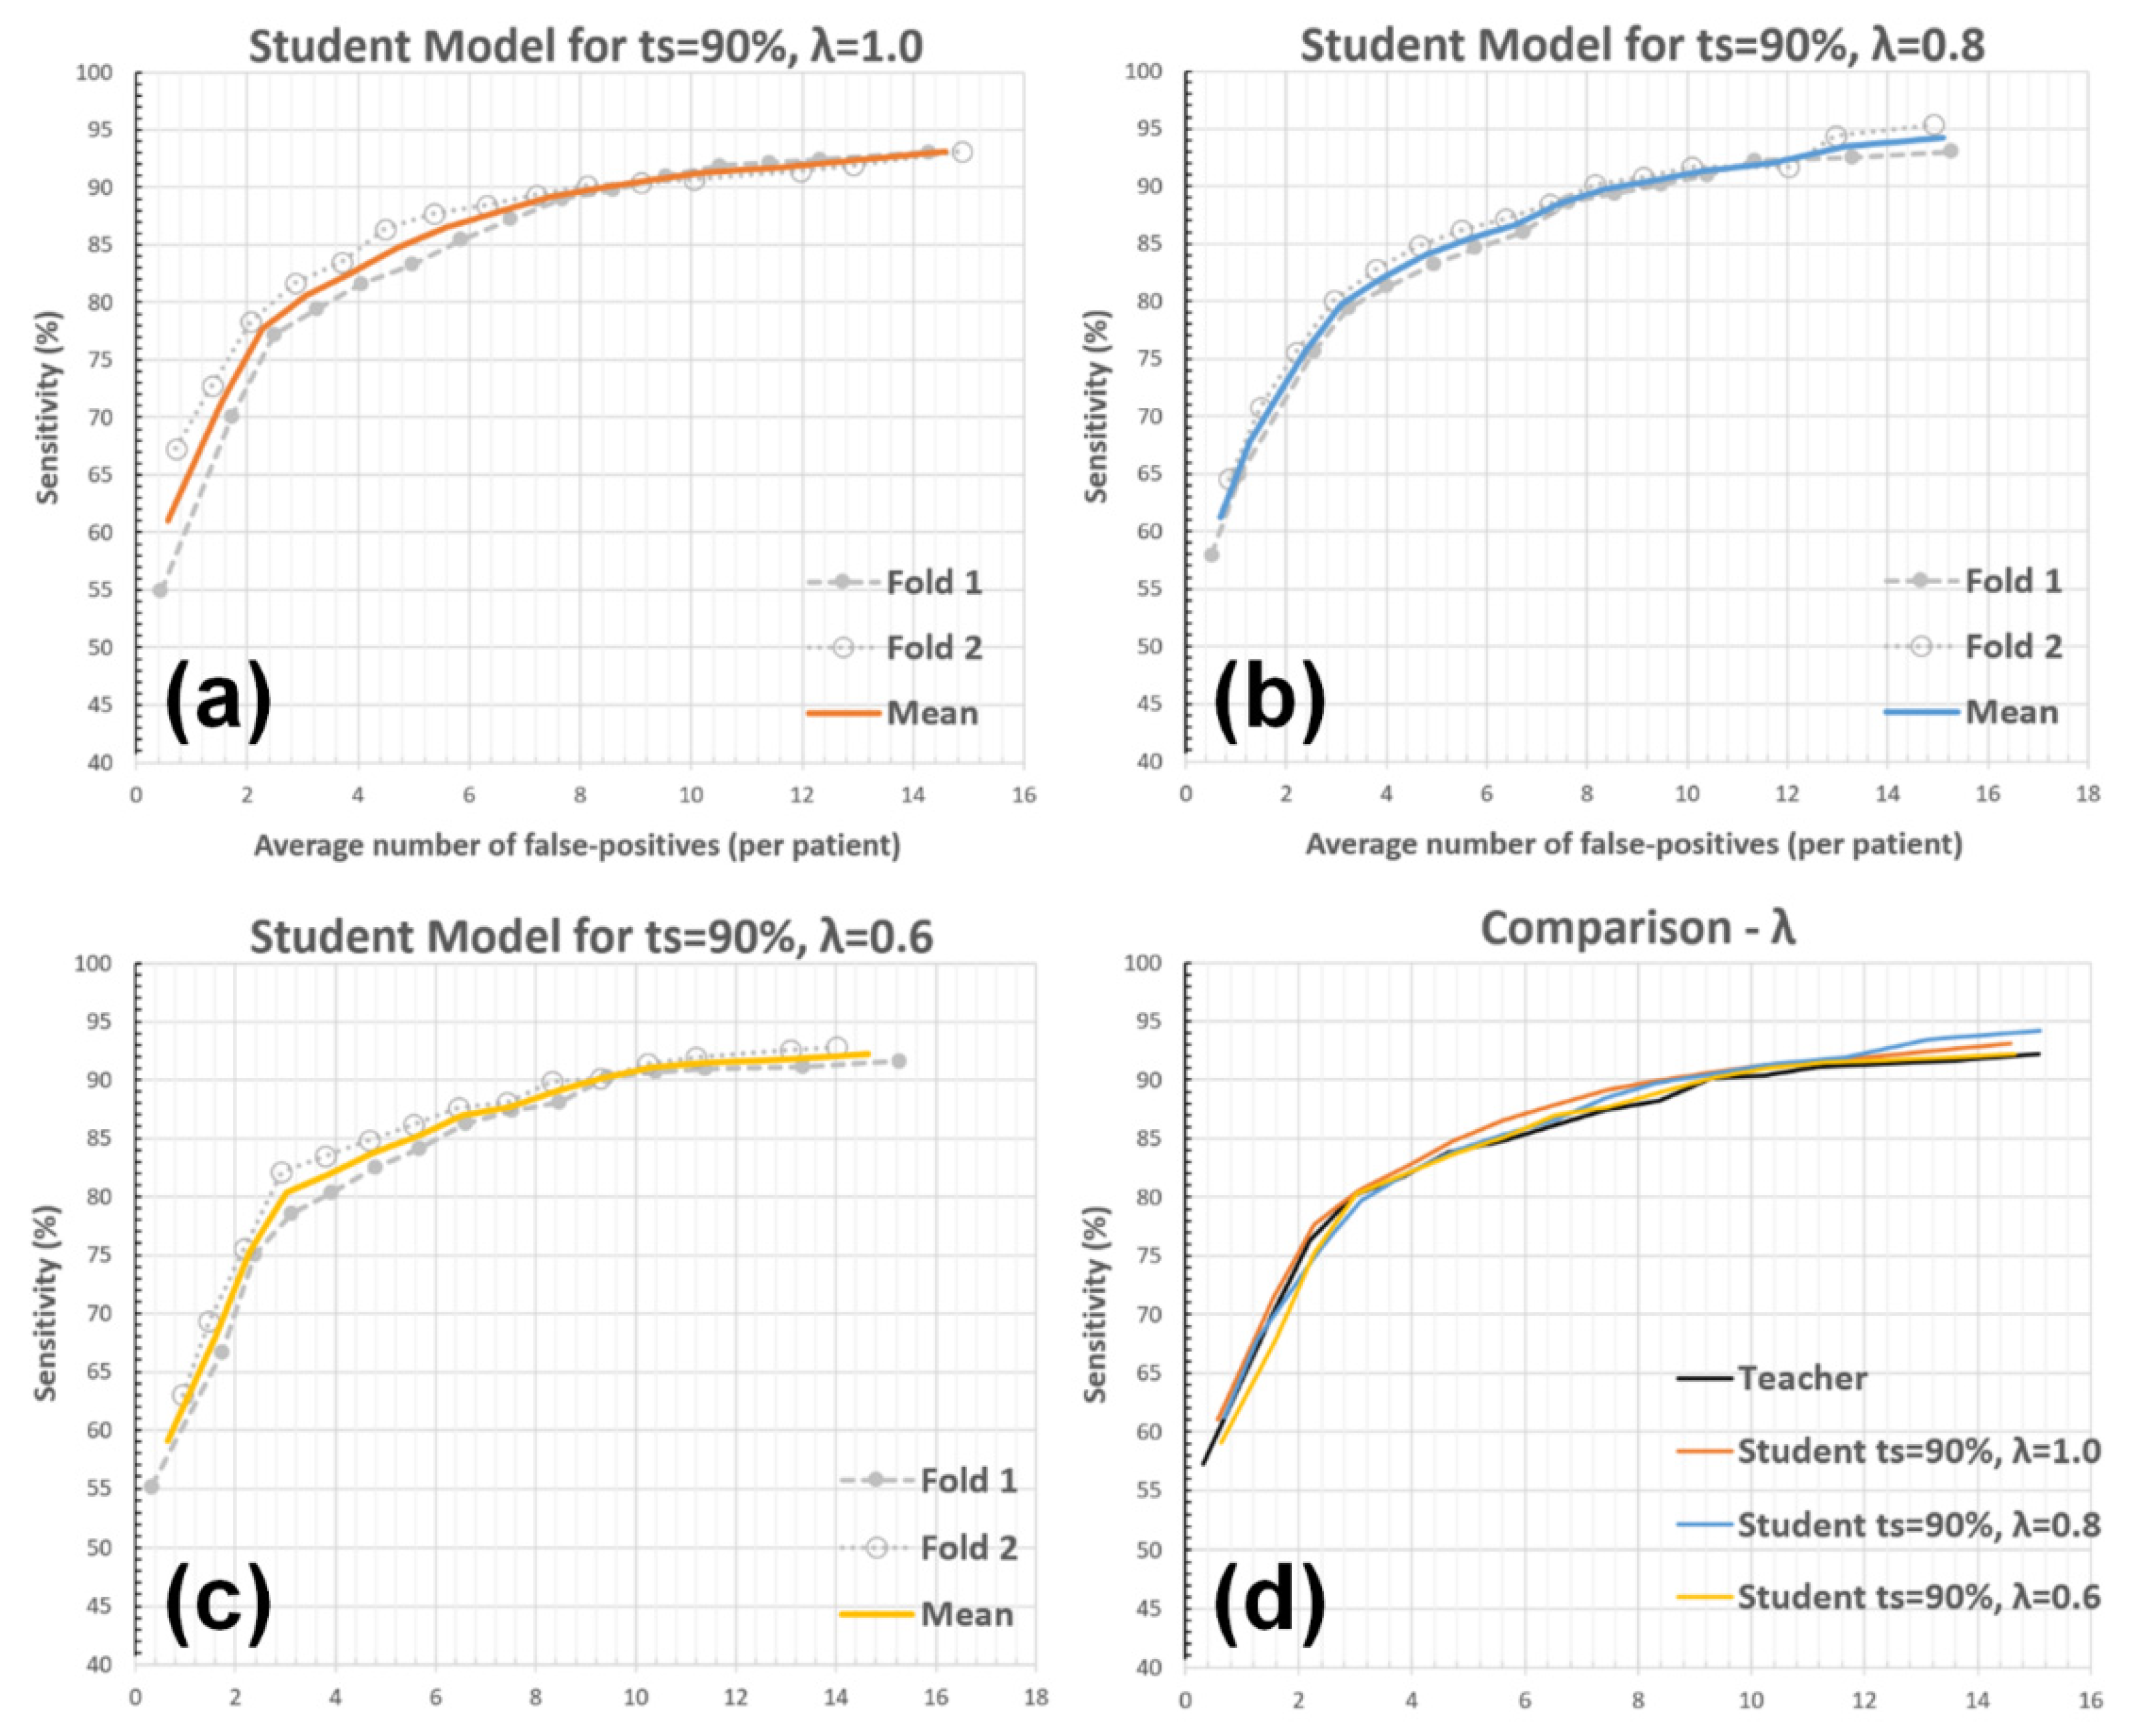

3.2. Experiments with System Parameters

3.2.2. Unlabeled Data Weights (λ)